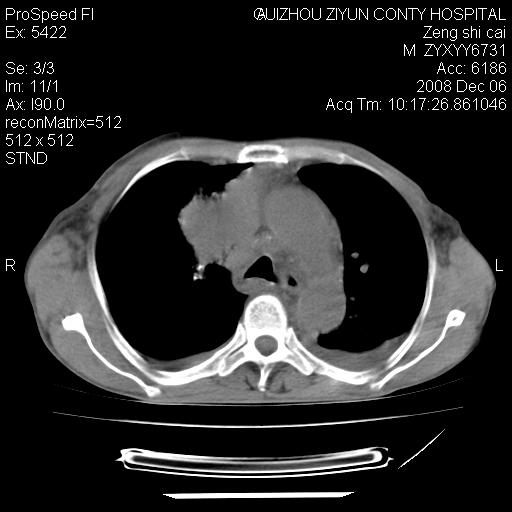

标题: CT16961:M、71岁,咳嗽半年,无血痰;胸片示右肺占位。 [打印本页]

标题: CT16961:M、71岁,咳嗽半年,无血痰;胸片示右肺占位。

右肺纵隔型肺癌伴纵隔淋巴结及胸膜转移!

右肺纵隔型肺癌伴纵隔淋巴结转移!双侧胸水!

1)考虑右肺上叶纵隔型肺癌伴纵隔淋巴结转移。2)心包积液,双侧胸腔积液。

右肺癌并纵隔淋巴转移,腹膜后转移可能性大,两侧胸腔积液

右肺上叶纵隔型肺癌伴纵隔淋巴结转移。心包积液,双侧胸腔积液。

右肺纵隔型肺癌伴纵隔淋巴结转移!双侧胸水\\心包积液